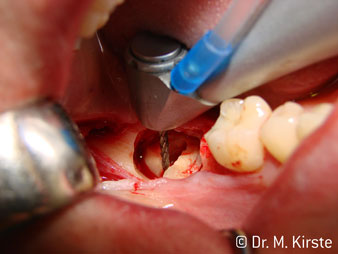

Die Winkelwahl des 45° Handstücks bringt viele Vorteile in der Anwendung. Chirurgisch tätige Kollegen, und für diese ist das Handstück in erster Linie entwickelt worden, werden schnell bemerken, dass man sehr gezielt arbeiten kann. Insbesondere bei der Weisheitszahnentfernung (Abb. 2) bedarf es keiner großen Weichteilabspreizungen im Wangenbereich (Abb. 3). Die Handstückkopfgestaltung kombiniert mit leichten Kopfdrehungen bei der Präparation lassen ein sicheres und schnelles Arbeiten im retromolaren Bereich zu.

Apropos schnelles Arbeiten: Es können über 100.000 U/min erreicht werden. Eine absolut professionelle Kühlung und ein kleiner Ansatzkopf lassen keine Fragen hinsichtlich thermischer Effekte oder übersichtlichem Arbeiten aufkommen.

Die professionelle Lagergestaltung im Innenleben des Handstückkopfes garantiert einen ruhigen Lauf der Bohrer, bei der Zahn- oder Wurzelseparation (Abb. 4 - 9) zeigt sich ein beeindruckendes Schnittbild ohne Schlageffekte.

Das 45 ° Winkelstück liegt sehr gut in der Hand. Man bemerkt sehr schnell, dass der Arbeitskopf dem Winkel des Zeigefingers nachempfunden und somit die gewünschte Bewegung nur einige gedachte Zentimeter parallel an die Spitze verschoben ist. (Abb. 1)“

Abb. 1